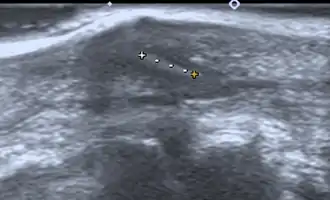

- Medical ultrasonography – used to locate glass, metal, pencil graphite, some plastics, stone, and some types of wood.[5]

Small wooden splinters (1–4 mm) distant from bones are most easily detected by ultrasonography, while CT scan and magnetic resonance imaging have higher sensitivity for those near bones.[6]